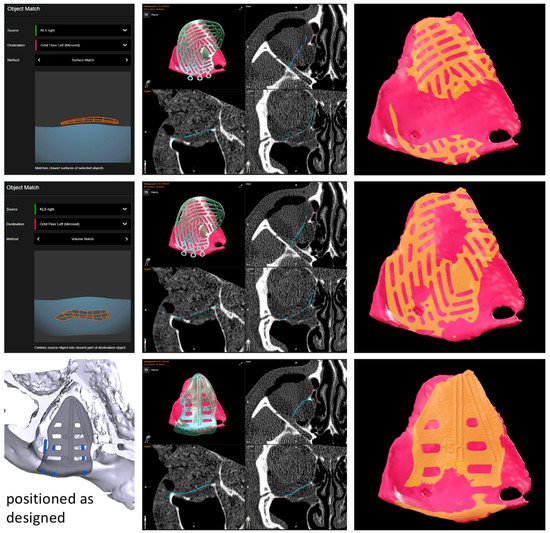

Virtual surgical planning involved loading the CT data set in the axial plane and bone window with a slice thickness of 0.75 mm into the software Brainlab Elements Contouring 4.5’ (Brainlab, Munich, Germany). After virtual mirroring of the healthy, unaffected site to the fractured site, the defect area was outlined. A standard pre-fabricated titanium mesh of the KLS Martin osteosynthesis system for orbital reconstruction was loaded into the data set from the software library. The titanium mesh was put into place by the option ‘object matching.’ This algorithm allows the use of two different methods: surface and volume matching. For surface matching, a point cloud is matched onto a given surface (for volume matching into another point cloud) by rotating and translating the point cloud to minimize the root mean square (rms) distance of the points to the surface (or volume, respectively). Surface matching is usually recommended for repositioning bones, and volume matching is usually recommended for replacing bones (e.g., after tumor resection). From a surgical point of view, orbital reconstruction allows repositioning of bone only in smaller defects that show small, displaced fragments still pedicled to the periosteum, while bigger defects must be reconstructed by replacing the lost bone fragments. That is why, in our experience, volume matching delivered better results as it aimed for a matching into the volume of the mirrored floor, thereby re-contouring the fractured orbit (see Figure 2). Surface matching, on the other hand, places the implant onto the mirrored floor, thereby over-contouring the orbital outline.

Figure 2.

Results of the object matching: the upper and middle rows showing the pre-fabricated titanium mesh put in place by surface (upper row) and volume (middle row) matching, while the lower row displays the geometry of the PSI design in its planned position. The right column displays the inter-sectioning volume (orange) of each reconstruction result with the mirrored orbital floor (pink). While the inter-sectioning volumes for the pre-fabricated titanium mesh were 0.07 cm3 for surface matching and 0.12 cm3 for volume matching, the inter-sectioning volume of the PSI was the biggest, with 0.14 cm3 offering the reconstruction result most true to the mirrored anatomy. Moreover, the areas of the supporting bone surfaces on which the titanium meshes rested were significantly smaller. This also applied to the distances between the supporting bone surfaces and the different titanium meshes, which showed no gap at all for the patient-specific implant.

The reconstruction result of the virtually positioned pre-fabricated titanium mesh was compared to the possible reconstruction result of a PSI. Therefore, the PSI design workflow was followed as described before [14,15]. The DICOM data set was sent to KLS Martin GmbH (Tuttlingen, Germany) via their online platform, IPS Gate. Designing steps were reviewed via online chat, including the definition of the outline of the PSI following the contour of the virtually reconstructed orbit and adding design features like drainage holes and navigational groves. The STL file of the final geometry of the PSI was provided by KLS Martin. The STL file was imported into the Brainlab data set, allowing direct comparison (see Figure 2).